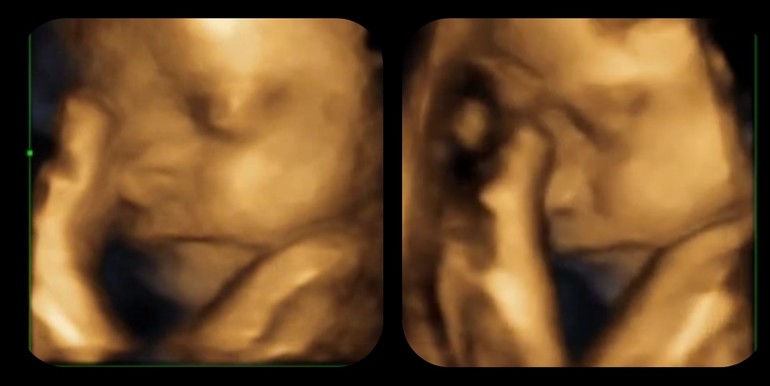

Фото 3д

УЗИ, КТГ, доплерВчера ходила на УЗИ скрининг третий, все у нас в норме.

И сделали фото и видео, до этого в 27 недель была на 3д.

Опять спала моя красотка, зато фото хорошо получилось😍

Это в 27 недель, скриншоты с видео

Это вчерашние

Срок 32+2

Вес 1958 по УЗИ